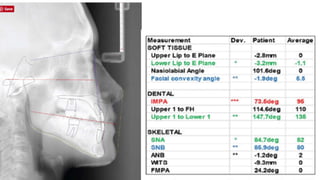

Cephalometric analysis revealed a strong Class III

component with severe dental compensation. At 73 degrees,

Cephalometric analysis revealeda strong Class III component with severe dental compensation. At 73 degrees, the lower incisors were retroclined approximately 20 degrees from the norm. Although ANB was only slightly negative, the Wits appraisal came out to -9.3mm. Because of the severity of the Class III skeletal component and the patient being in active growth, the likelihood of future surgery was discussed before any treatment.